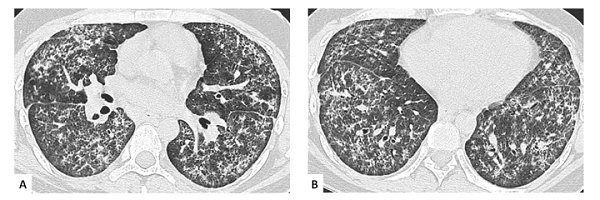

常见的肺部病变是:间质性肺炎,发生率>40%。

多呈缓慢发展,可有不同程度的干咳、呼吸困难,易继发感染。

少数患者的肺间质病变以急性型出现,表现为急性发热、呼吸困难、发绀、干咳。

个别还可出现气胸、纵隔积气甚至广泛的皮下气肿。